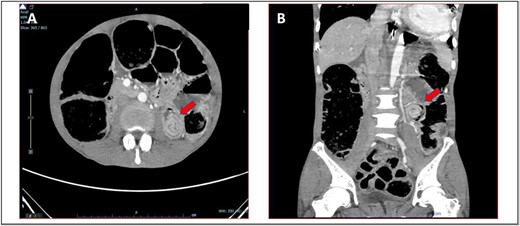

A 52-year-old Malay man, an active smoker, with underlying pulmonary hypertension secondary to atrial septal defect secundum with Eisenmenger syndrome and chronic lung disease. He had been experiencing symptoms of intestinal obstruction for a week. He had abdominal pain for 1 day, vomiting for 2 days, and unable to pass motion for the past 1 week. Patient was tachypnoeic with a respiratory rate of 35/min, a pulse rate of 116 bpm, and SPO2 of 90% under high-flow nasal cannula 50%/50 L. Abdominal radiograph showed dilated large bowel. Computed tomography abdomen and pelvis revealed short segment circumferential enhancing bowel wall thickening at rectosigmoid region causing intraluminal obstruction and presence of target sign at left lumbar region suggestive of jejunojejunal intussusception (Figs 2 and 3).

(A) Axial view and (B) sagittal view of computed tomography showed short segment circumferential enhancing bowel wall thickening at rectosigmoid region causing intraluminal obstruction (red arrow).